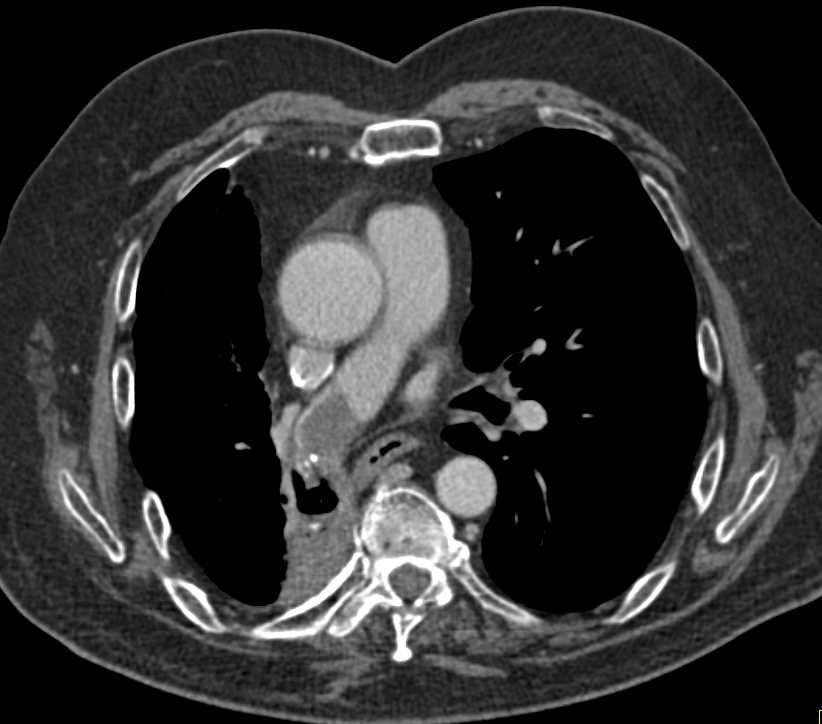

CCTA: Right Coronary Artery Arises off the Left Cusp